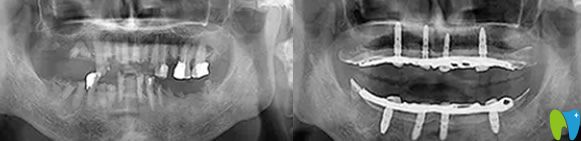

到院后,譚院長(zhǎng)通過CT進(jìn)行數(shù)據(jù)采集,電腦精密計(jì)算人工牙根的植入位置,精準(zhǔn)制定種植方案,先把種植體種在牙槽骨內(nèi),然后再等恢復(fù)。外婆年紀(jì)大了,父母總擔(dān)心,種植過程中疼痛怕她承受不了。譚院長(zhǎng)說我們的擔(dān)心都是多余的,會(huì)緊張那是必然的,手術(shù)是通過高氧恢復(fù),能夠讓高齡老人種牙后得到更好的調(diào)養(yǎng),真正實(shí)現(xiàn)無痛種牙。

種植前CT效果: